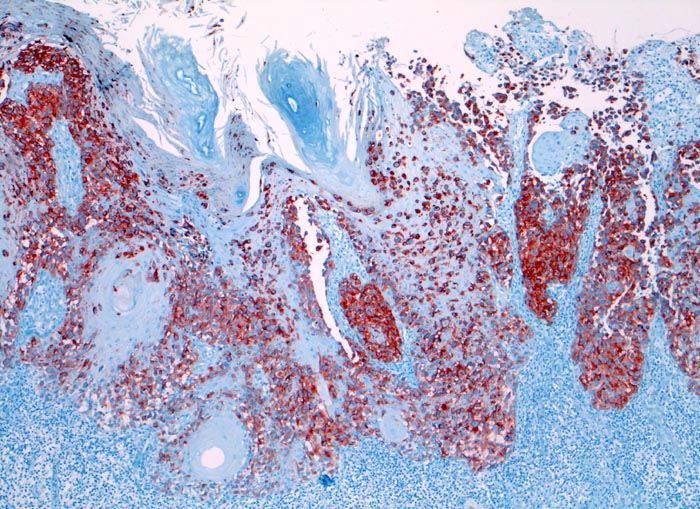

amelanotisches akral lentiginöses Melanom

Haut, Hand palmar, Finger

Die Melanomzellen färben sich an mit dem Melanommarker HMB-45. Dabei wird die Ausdehung der Tumorzellinfiltrate deutlich. An der Oberfläche sind die Zellen diskohäsiv.

Makroskopisch ulzerierte Läsion mit hellbraunem Grund.

Immunhistochemie

HMB-45